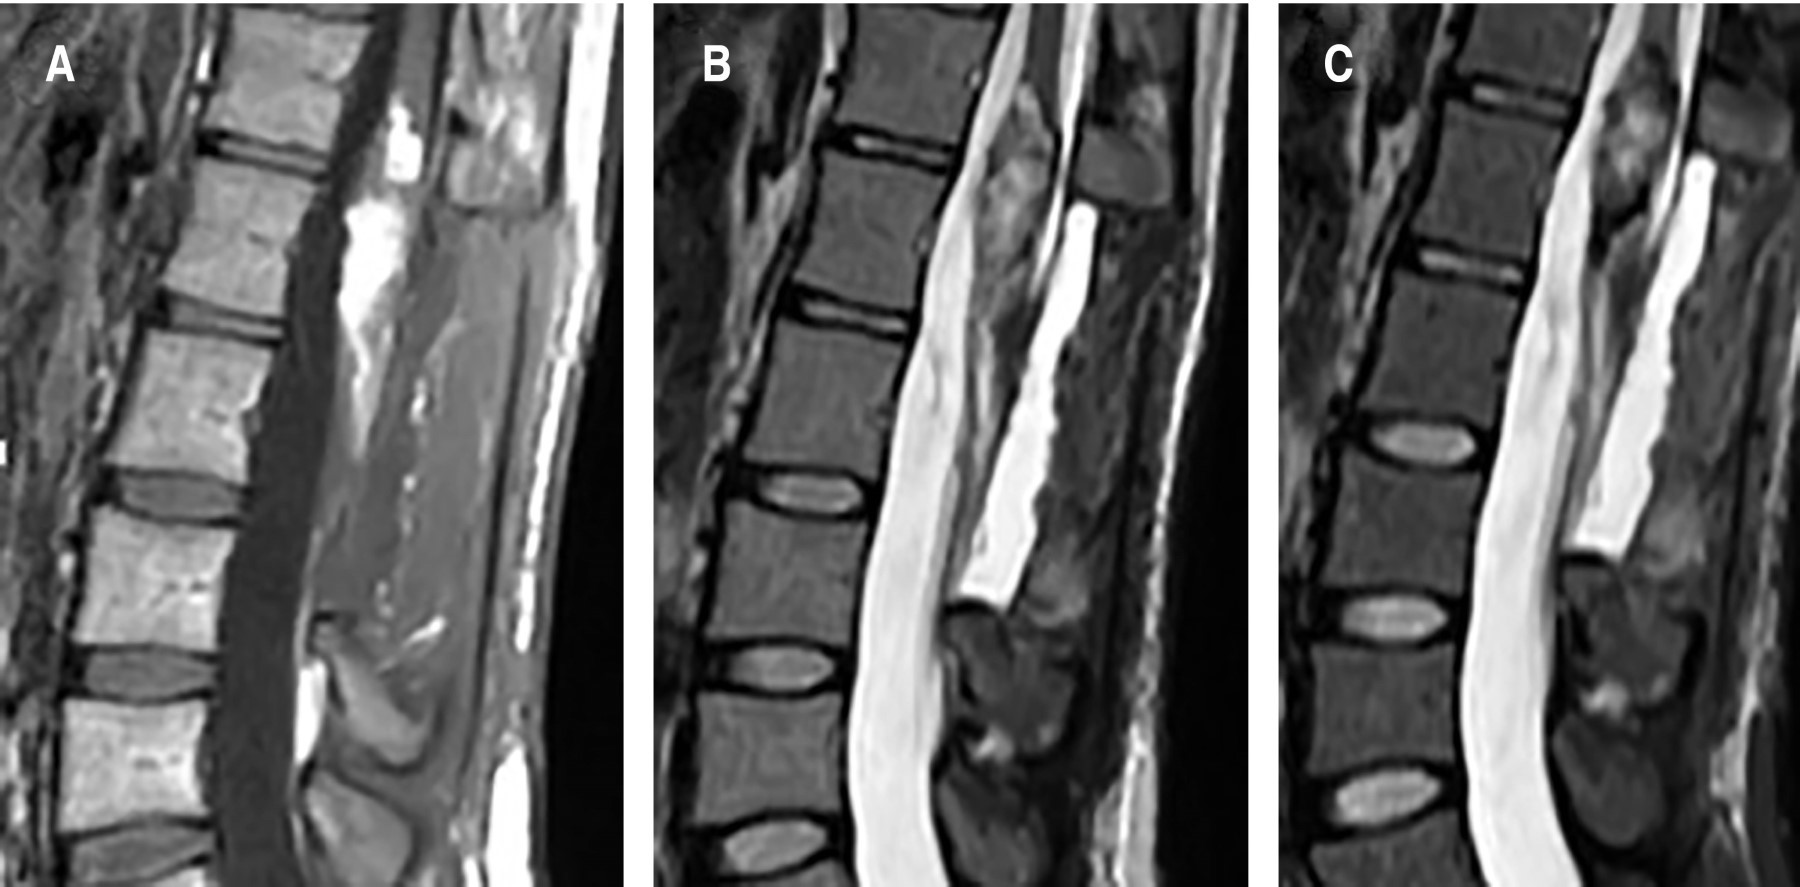

Female patient, 26 years old, with a history of pain in the right pelvic member of six years of evolution, with progressive claudication, repeated urinary tract infections, emergency urinary incontinence, admission to the emergency service, with an incidentally finding an intramedullary cyst from the vertebral body T12 to L3, with heterogeneous enhancement with intravenous contrast (Figure 1). Surgical resection was performed with neuro monitoring and posterior approach, laminectomy of L1 and L2, with the finding of an intradural extramedullary encapsulated macroscopically with pearled appearance, dismissable consistency, and easily resectable. Satisfactory macroscopic resection was performed, leaving a small remnant attached to the medullar cone (Figure 2). The histopathological report of the lesion was abundant keratin, compatible with a dermoid cyst (Figure 3). The patient left the hospital two days after the procedure, without sensory or motor deficit in the lower limbs, in follow-up at 2 weeks showed improvement in urinary incontinence. Postoperative magnetic resonance imaging was performed where a small remnant is observed at the level of the spinal cord cone (Figure 4).